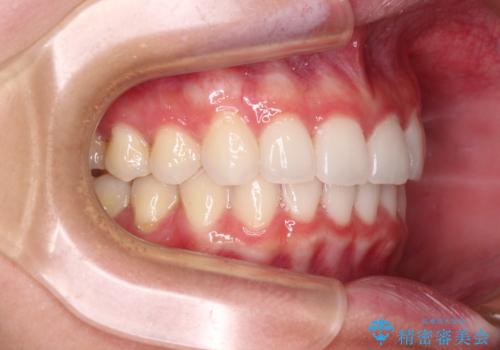

- 前歯2本が飛び出してることを気にして来院された患者様です。

全体的に黄ばんだ歯の色も気になるとのことで、マウスピース矯正により飛び出した前歯を治しつつ、ホームホワイトニングを併用して黄ばみを解消していくこととしました。

歯と歯の間を削ることで、飛び出した前歯が引っ込み、スッキリとした口元となりました。

歯の黄ばみも改善され、明るい歯並びとなりました。